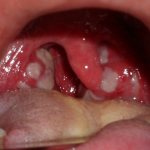

На фото видно, что при тонзиллите на миндалинах появляются желтые точки. Во время обострения данного признака нет. Это означает, что имеет место быть фолликулярных абсцесс.

Бактериальный тип патологии – это тот, что вызван деятельностью бактерий. Для лечения обычно применяют антибиотики. На фоне такого поражения может возникнуть гнойный тонзиллит, при котором экссудатом покрываются воспаленным миндалины, как это видно на фото.

На этой стадии заболевания на миндалинах образуются узелки желтоватого цвета. Врачи называют это явлением «звездного неба». Лимфоузлы увеличены и болезненны. Продолжительность болезни – не более недели.

Примечание! При лакунарной ангине возникают те же симптомы, но миндалины еще покрываются белыми наростами гнойного характера. Тонзиллитные пробки легко удаляются, а ткани после этого не кровоточат.